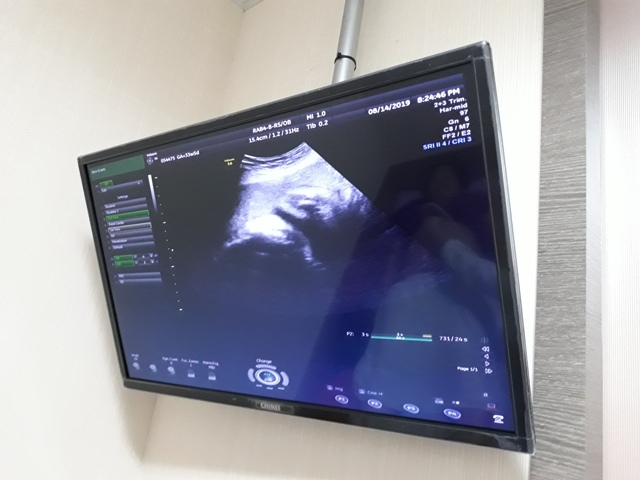

當小純進入診間看診時,我並沒有進去,因為小純說,有時男生不能進去,會被請出來。在外頭等待的我感到很緊張,不久之後,謢理人員請我進入診間,我嚇了一跳,想說發生什麼事了,進入之後,得知小純真的懷孕了,而且已懷了九星期又五天。看診的醫師說,驗孕棒第二條線淡淡的,沒想到胚胎照出來那麼大了,說Baby很健康。還說一閃一閃的是他的心跳,有頭、有手、有腳還有臍帶。小純後來說看了內心覺得很感動,才叫我一起進去看。

小純肚子裡的Baby超音波圖↓